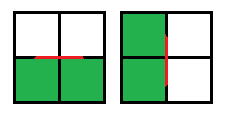

Каждый раз мы будем находится в каком-то узле, и нам необходимо очертить контур вокруг “положительных” квадратов. Для принятия решения мы будем рассматривать знаки четырех соседних квадратов: левый верхний, левый нижний, правый верхний, правый нижний. Если исключить симметрию, то нас интересует три случая.

1. Три квадрата одного знака и один противоположного, движение контура происходит по диагонали:

2. Два квадрата одного знака и два противоположного, причем квадраты с одинаковым знаком находятся по одну сторону, движение контура идет вертикально или горизонтально:

3. Два квадрата одного знака и два противоположного, квадраты с одинаковыми знаками размещены по разные стороны:

Это является исключительным случаем, чтобы принять решение берется среднее значение интенсивности во всех четырех квадратах, и если оно больше или равно порогу, то центр положителен, в остальных случаях — отрицателен. Также важно какой узел является текущим в данный момент:

Алгоритм марширующих квадратов точно и однозначно строит контур. В примере ниже я специально смещал линию от центра стороны, чтобы был отчетливо виден каждый шаг.

Конкретно первый и второй случаи: